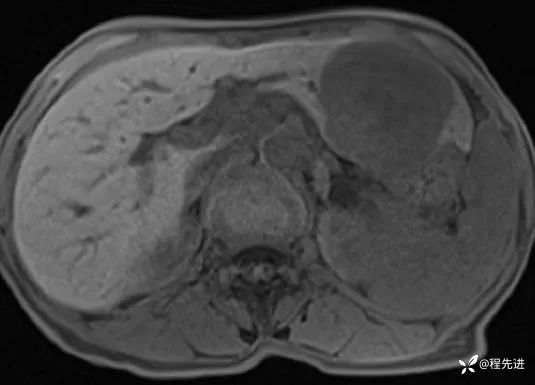

CT平扫: